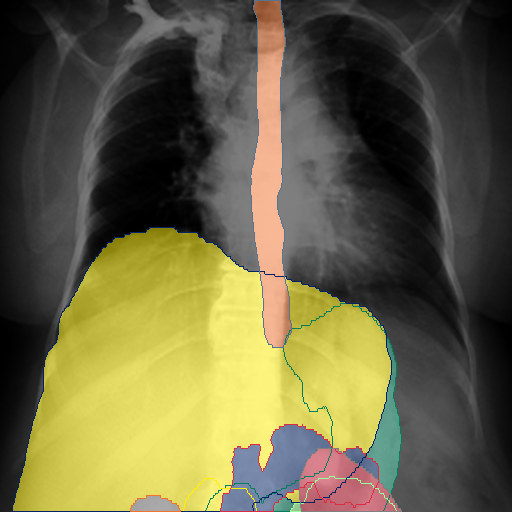

We show qualitative results for frontal projections in Fig. 2. We show a subset of classes belonging to the supercategories lungs, vascular systems, bones, and abdomen/digestive system. The predictions show minor deviations at the boundaries of the individual classes of the respiratory and vasculature system, while some inaccuracies become visible in the abdominal area. The qualitative results for the lateral projections are displayed in Fig. 2. Akin to the frontal view, the predictions show smoother borders but align with the ground truth. Apart from this, the segmentations provide matching insights on the thoracic anatomy with a slight deviation from the ground truth for both frontal and lateral views.

We display qualitative results in Fig. 3. The annotators tend to be content with most annotations. There are edits at the extensions of the esophagus, trachea, and aorta and corrections of the lower ribs. There is little consensus for classes in the abdominal area, such as the stomach, as seen on the right of Fig. 3 . In contrast, the annotators often align for bone classes.